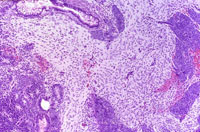

Neurological tissue is clearly present in this view.